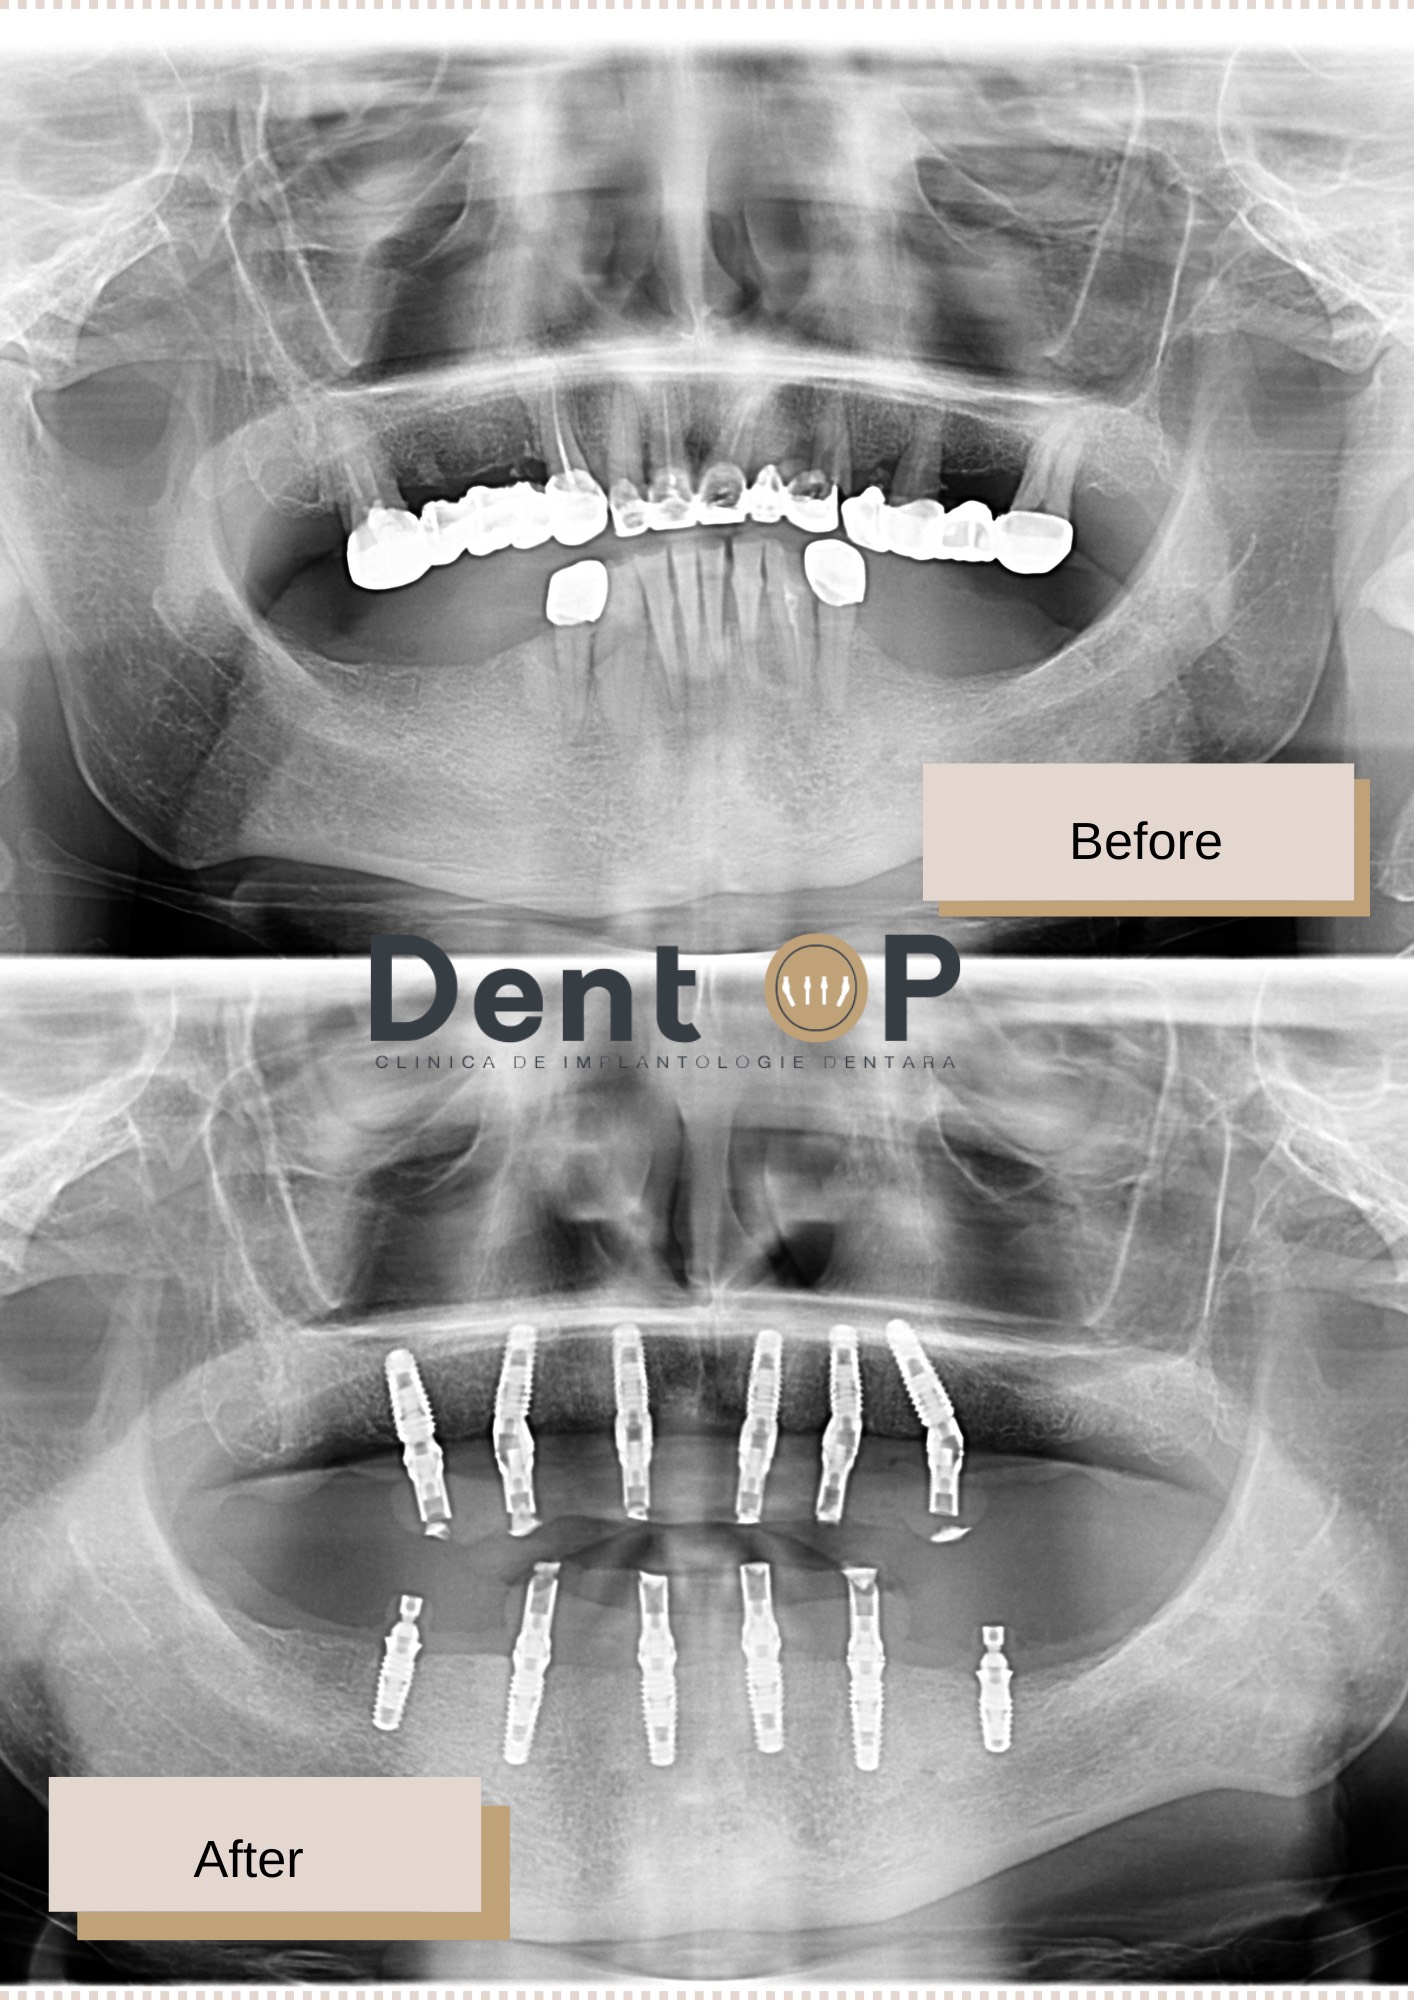

Ce am ales să facem în cadrul clinicii de implantologie dentară DentOP a fost să analizăm cazul clinic al domnului N. Astfel, dr Cazacu Corrado – Medic Specialist Chirurgie Dento-Alveolară a recomandat inserarea a 12 implanturi dentare (6 la maxilar și 6 la mandibulă) într-o singură ședință cu Sedare Conștientă.

Rezultatul este unul uimitor. În doar 24h, domnul N. a primit o dantură provizorie pe care a purtat-o timp de 4-6 luni, iar apoi i-a fost fixată lucrarea definitivă pe care o va purta cât mai mult timp.